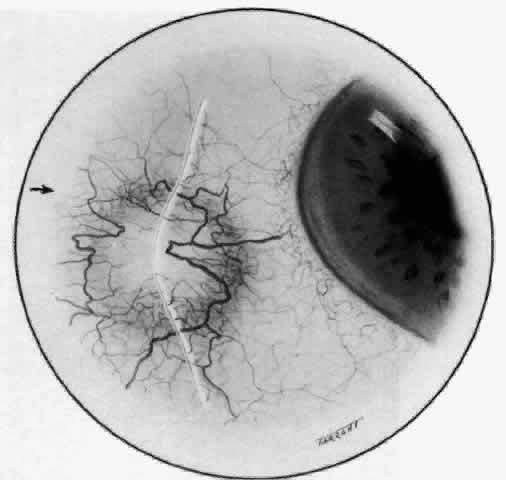

The sclera that is edematous is pushed forward, and the deep episcleral network is more congested than the superficial networks (Figs. 27 and 28). It is usually easy to ascertain by simple observation that the patient has scleritis and not episcleritis. However, it is not as easy to ascertain whether the patient has early necrotizing scleritis. It is in these patients that fluorescein angiography has considerable value, because the first changes are detectable in the ocular vasculature. Prompt and adequate treatment can prevent these changes from becoming irreversible.

Fig. 27. In scleritis, maximum congestion occurs in deep episcleral plexus, which is bowed forward by underlying scleral edema. Episcleral tissue is slightly infiltrated and superficial plexus is slightly congested (see Fig. 14). (Watson PG, Hayreh S, Awdry P: Episcleritis and scleritis. Br J Ophthalmol 52:278–279, 1968)

Fig. 28. Nodular scleritis. Both the anterior conjunctival slit and the deep scleral slit are displaced forward by the scleral edema. There is little separation between these two beams, indicating that all the edema is in the sclera and not in the overlying episclera. (Watson PG, Hayreh S, Awdry P: Episcleritis and scleritis. Br J Ophthalmol 52:278–279, 1968)